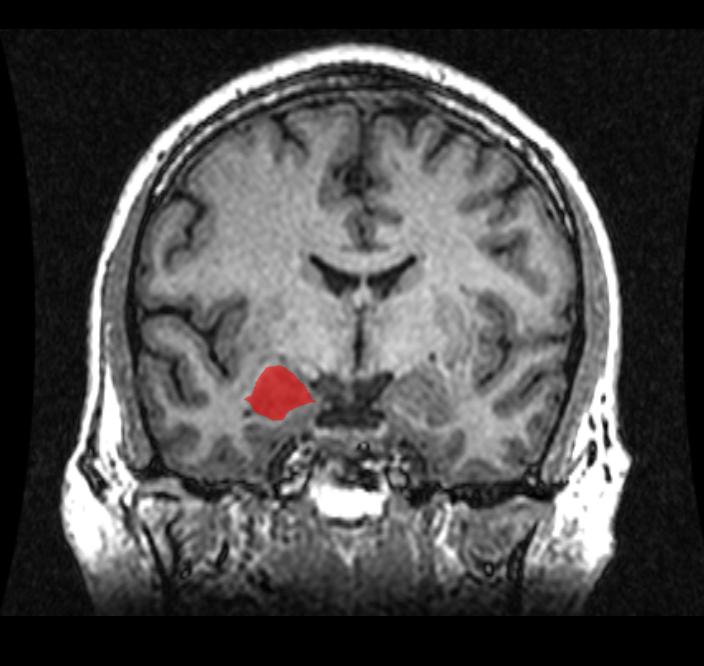

The olive-sized amygdala is a key brain structure involved in all types of emotion and in social behaviors such as aggression and sexual arousal. Animal studies and early MRI reports indicated that the amygdala is disproportionately larger in males' brains. Such a size difference has been suggested to contribute to sex differences in emotionality and in the prevalence of disorders such as anxiety and depression.

The report is co-authored by RFU medical students Dhruv Marwha and Meha Halari, who worked with Eliot to systematically identify all MRI studies of the human amygdala over the past 30 years. They found 58 published comparisons of amygdala volume in matched groups of healthy men and women (or boys and girls) that included 6,726 total participants. Studies reporting raw amygdala volume show that the structure is indeed about 10 percent larger in male brains. However, this difference is comparable to males' larger body size, including the 11-12 percent larger volume of males' brains overall. Among studies that reported amygdala volumes corrected for overall brain size, the volume difference was negligible (<0.1 percent in the right amygdala, 2.5 percent in the left amygdala) and not statistically significant.